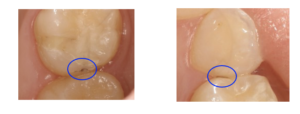

こんな小さな虫歯でも発見できます

むし歯 虫歯

当院では、技と勘に頼るだけの診査ではなく、レーザーで正確な診査を行い、虫歯を数値化します。

ダイアグノデントは、歯に当てたレーザー光の反射を解析し、

数値と音色に置き換えて読み取り、歯質の変化、虫歯の状態を調べます。

特に見つけるのが困難とされる奥歯の溝の診断に有効で、個人のリスクを考慮しながら、

予防(再石灰化など)や処置・管理(最小の切削)を行うことができます。